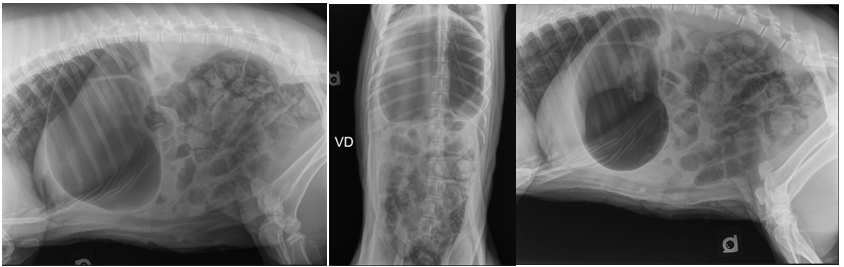

A 4-year-old, 27 kg, castrated male potbelly pig with a 24 hour history of anorexia, decreased water intake, vomiting, decreased fecal production, and shivering was presented to the Food Animal and Camelid Hospital, Iowa State College of Veterinary Medicine for evaluation. These clinical signs were noticed shortly after the pig was found to have consumed a portion of a blanket used as bedding. Upon presentation, the patient was bright, alert, responsive, and inquisitive of the environment, although demonstrated several indicators of pain including postural changes.1 The pig had an ideal (2.5/5) body condition score based on a scoring system for commercial pigs.2 The patient was sedated with intramuscular midazolam (0.5mg/kg) and ketamine (1mg/kg), and maintained under general anesthesia with 2% isoflurane inhalant and oxygen (2L/min) via mask to facilitate physical examination. Incidental physical examination findings included oral malocclusion due to an elongated permanent lower right canine tooth as well as moderate alopecia over the dorsum and bilateral dark brown ocular discharge with mild conjunctivitis. The remainder of the physical examination was unremarkable. Whole blood was collected from an auricular vein for a complete blood count (CBC) and serum chemistry. The pig’s CBC revealed hemoconcentration with a hematocrit of 56% (normal 28.2-42.6%) and remaining CBC parameters were otherwise unremarkable. The pig’s serum chemistry revealed hypokalemia (2.8mEq/L, normal 4.0-7.0) and azotemia (creatinine 3.0mg/dl, normal 0.5-2.7mg/dL) but was otherwise unremarkable. Reference ranges from the Iowa State University Clinical Pathology laboratory were utilized. While under general anesthesia, three-view abdominal radiographs were obtained and revealed linear soft tissue opaque material in the proximal duodenum as well as a severely gas distended stomach (Figure 1). The remainder of the gastrointestinal tract was moderately diffusely dilated with gas and regions of heterogeneous soft tissue material. Differentials for this moderate diffuse dilation included severe enteritis or secondary to additional site(s) of small intestinal mechanical obstruction. Isoflurane was discontinued and the patient was allowed to recover from general anesthesia.

Figure 1 Right lateral (A), ventrodorsal (B), and left lateral (C) abdominal radiographs showing severe gas dilation of the stomach and moderately to severely diffusely dilated intestines with gas and soft tissue opaque material. In the left lateral projection (C), an amorphous and heterogenous soft tissue and gas opaque feature is noted in the proximal duodenum.